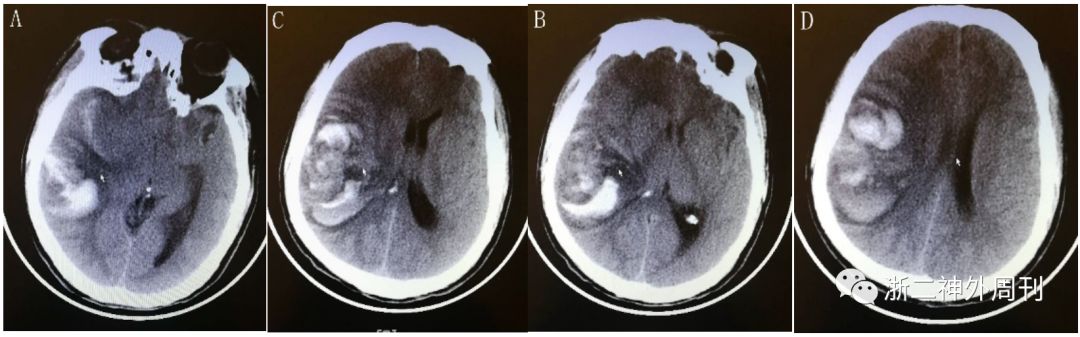

患者,男,39岁。2017.4.26因“突发头痛半天”至当地医院就诊,查头颅CT:右侧颞顶叶出血破入外侧裂,当天转至当地上级医院,拟诊“右侧颞顶叶脑出血破入外侧裂”入院。入院后急诊头颅CT示右侧颞叶血肿,伴蛛网膜下腔出血(图1)。因病情急重,未行MRI检查。

图1.头部CT平扫示右侧颞顶叶出血破入外侧裂。